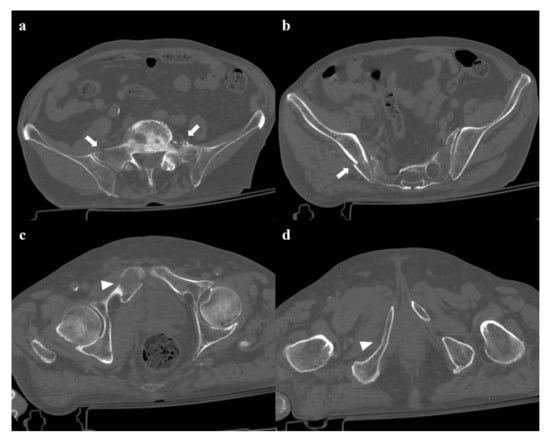

• Grade 1: compression fracture of the sacrum on the side of the impact, and transverse fracture of unilateral or bilateral pubic branches (Figure 1). Lateral compression grade 1 injuries are stable and have a nonoperative management [3].

• Zone II: the fracture involves the neuroforamina (Figure 1). In 28% of cases, there is an ipsilateral neurological deficit.

Figure 1. Lateral compression fracture, type 1. Axial computed tomography (CT) images show a fracture of the right-side superior and inferior pubic rami (arrows in (a,b)), and ipsilateral fracture of the sacrum (arrowheads in (c)); the sacral fracture involves the neuroforamina (zone II). Three-dimensional volume-rendering CT reconstruction in anteroposterior (AP) view confirms the type of fracture (d).